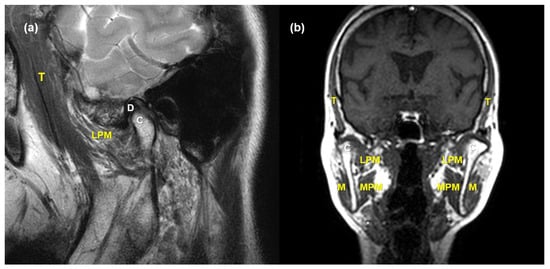

2.2. MRI Acquisition and Analysis

2.3. Validation of MRI Findings